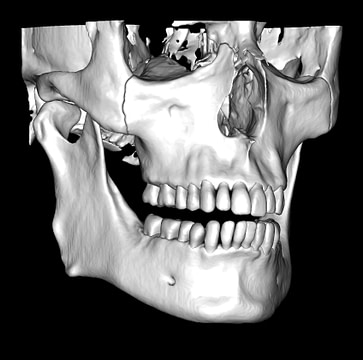

CBCT Segmentation into STL

Generate STL files from CBCT DICOM data.

Generate maxilla and mandible in one STL file or face, teeth, maxilla, mandible, airway, cranial base, canals as separate STL files.